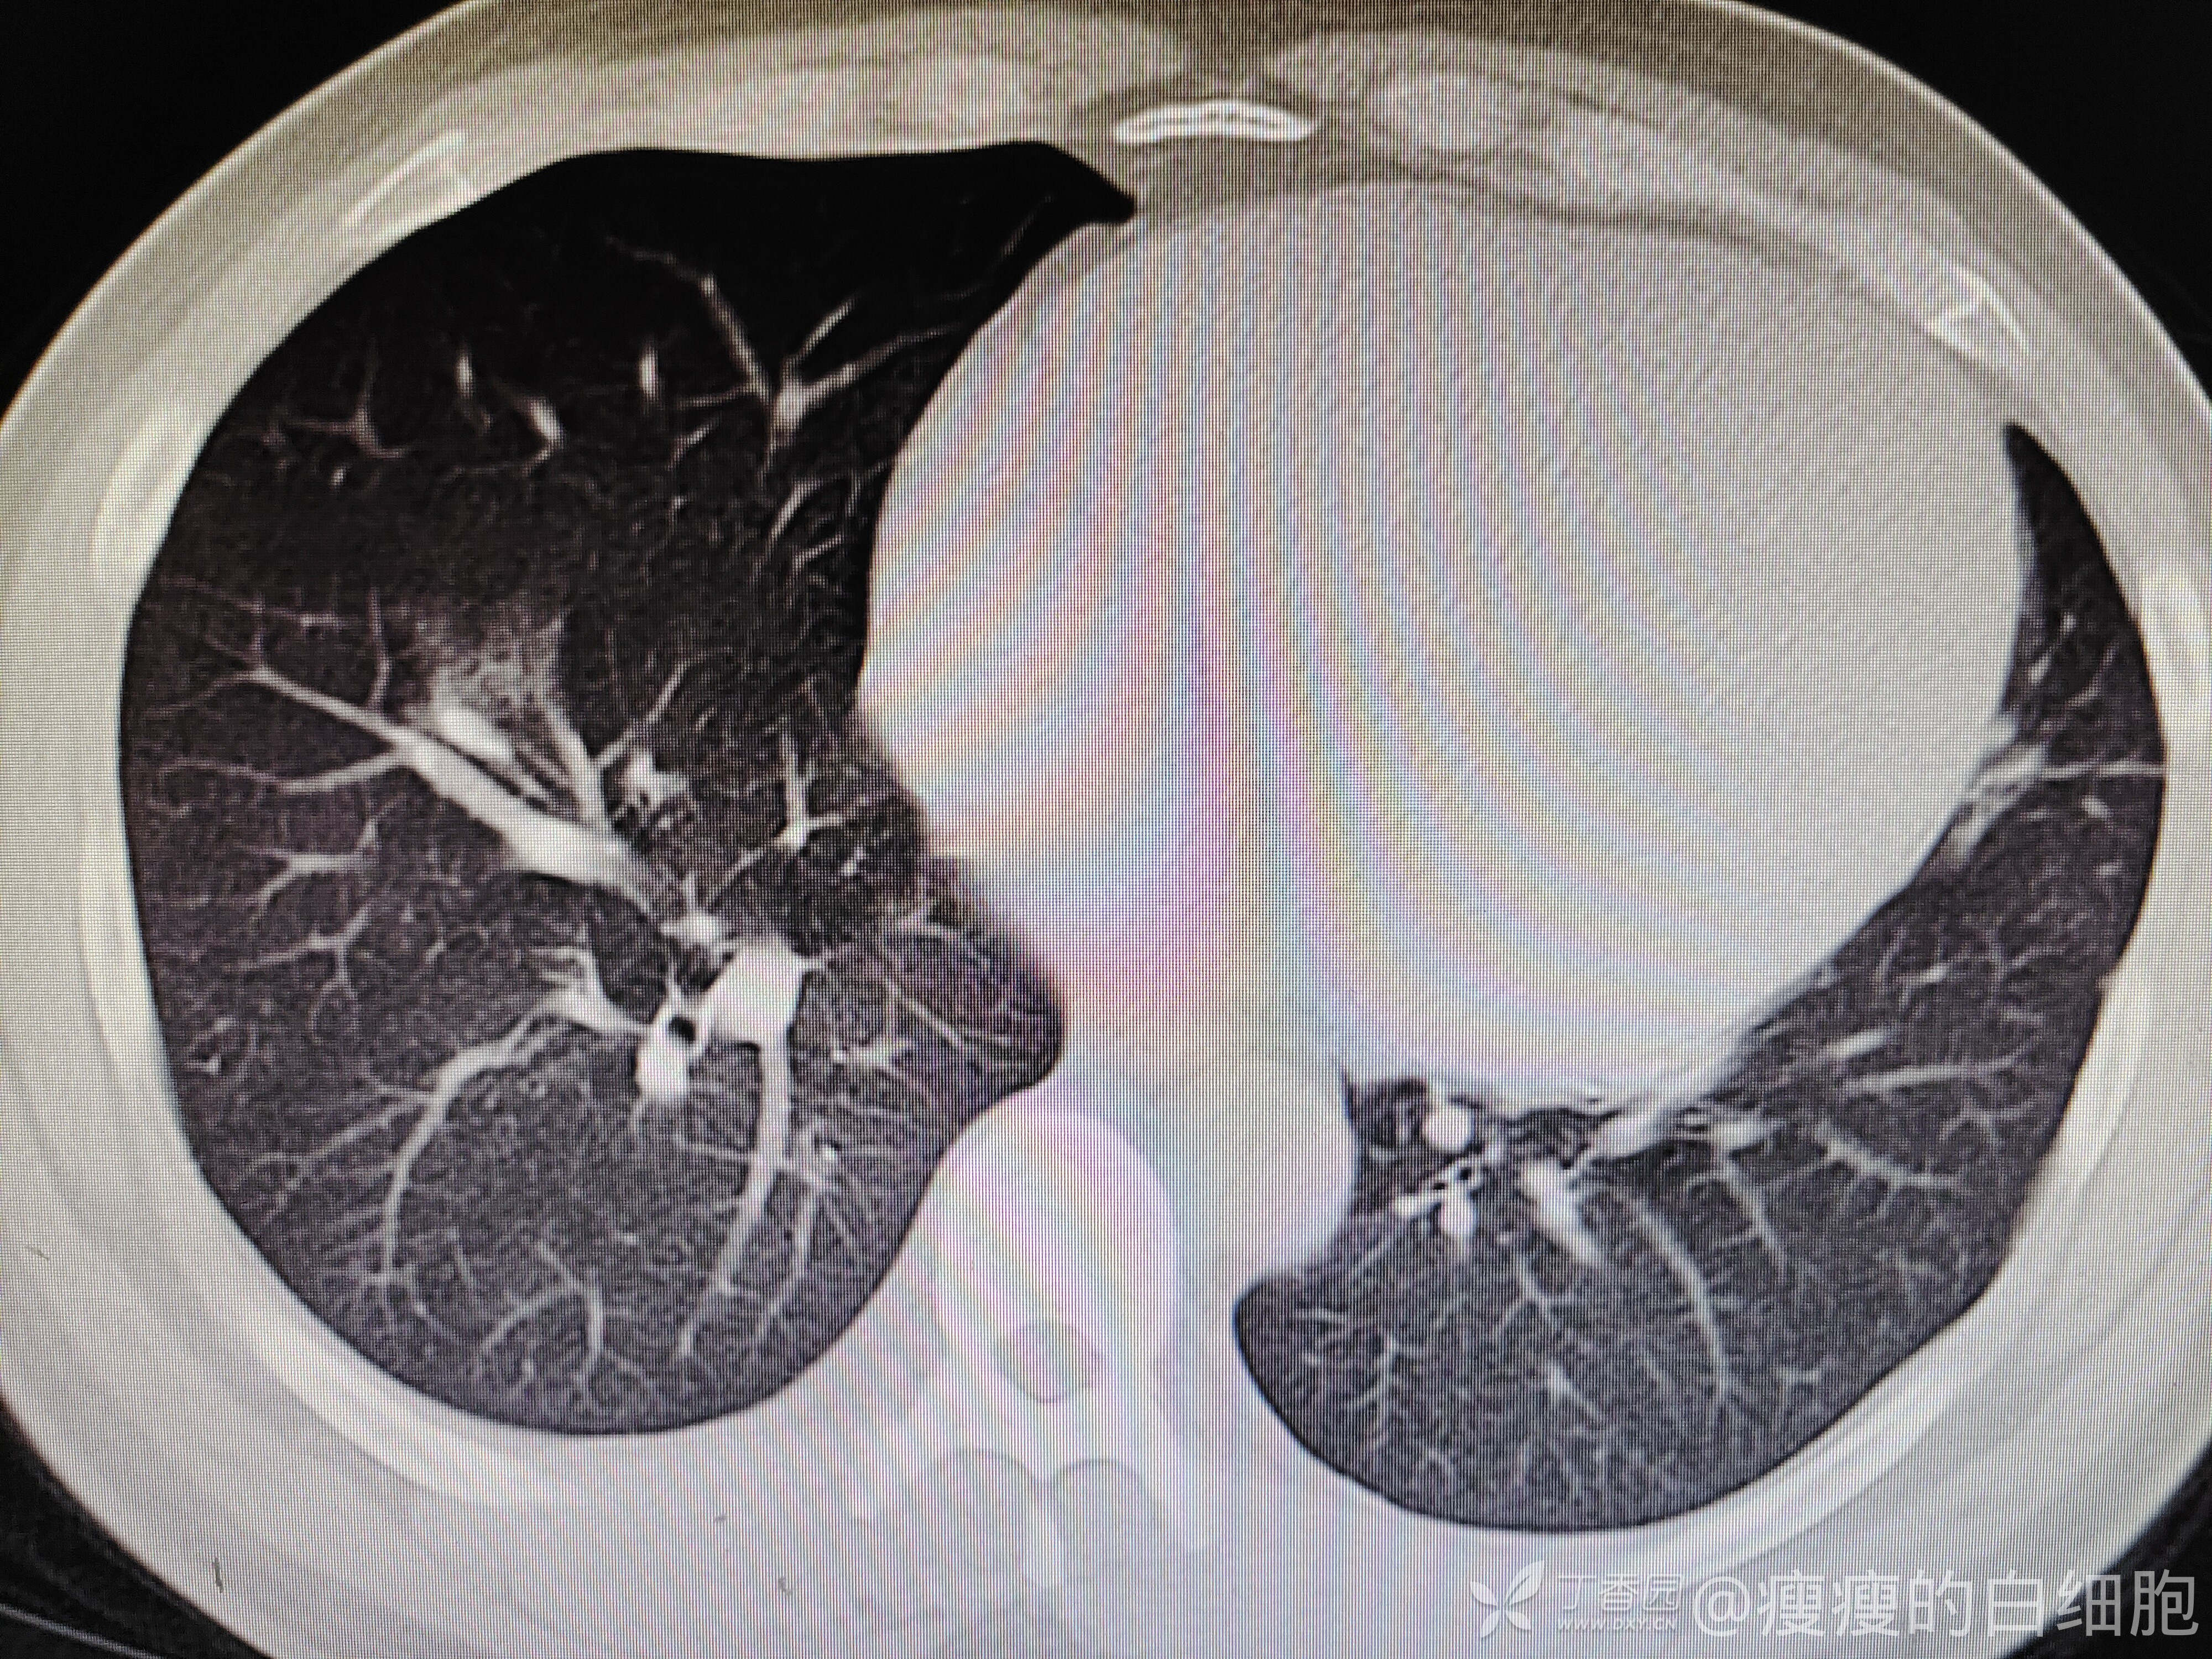

5天后咳嗽略减轻,但感胸闷。这时候血压达到了169/126mmhg,查体肺部无干湿性啰音,下肢也无水肿。再次复查胸部CT

新发病毒感染?还是心衰?继续完善检查,心电图大致正常。